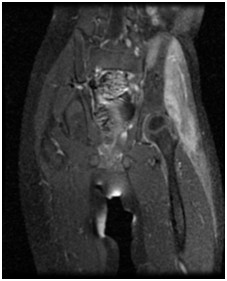

Figure 7 Coronal MRI of the pelvis fat suppressed T1WI: Diffuse marrow edema within the right femoral head and neck, as well as the acetabulum which extends to involve AIIS. There is destruction of the posterosuperior femoral head and adjacent acetabulum. A large joint effusion is present. Para-acetabular muscle edema is noted which involves the gluteal muscles most severely.